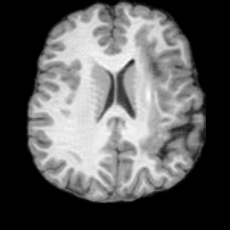

PathologicalHealthyDifferencew/o ACGw/ ACG(a)Refer to captionRefer to captionRefer to captionRefer to captionRefer to captionHealthyPathologicalDifferencew/o ACGw/ ACG(b)Refer to captionRefer to captionRefer to captionRefer to captionRefer to caption

Figure 6: Ablation study of Anatomy Consistency Guidance (ACG): (a) pathology-to-healthy; (b) healthy-to-pathology. Without ACG, edits cause anatomical inconsistencies outside lesions (arrows), whereas ACG keeps modifications lesion-focused.

Anomaly Consistency Guidance. Fig. 6 demonstrates the effectiveness of the proposed Anatomy Consistency Guidance (ACG) on bidirectional editing. Without ACG, the generated brains exhibit noticeable and unrealistic anatomical deformations in non-lesion regions (arrow-indicated), leading to structural inconsistencies between the edited and original brains, as shown in the corresponding difference maps. After incorporating ACG, the model effectively constrains editable modifications within pathological regions, while preserving the remaining anatomy. Tab. 4 further reports their quantitative performances: removing ACG leads to a substantial degradation in all L1, PSNR, and SSIM scores, reaffirming the critical role of ACG in achieving more accurate and structurally consistent reconstructions.